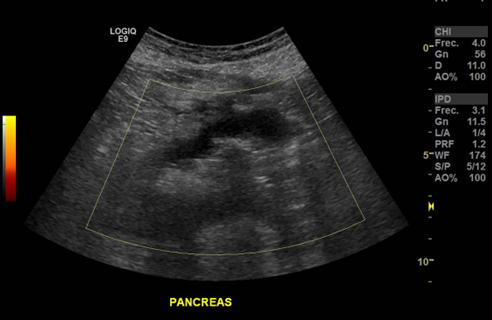

Páncreas hipoecogénico, heterogéneo, de bordes irregulares.

Líquido libre adyacente (Edema)

Hallazgo sugerente: Pancreatitis Aguda

Páncreas heterogéneo con líquido libre peripancreático

Signos de Pancreatitis Aguda.

• Difusa: Aumento de tamaño del Páncreas, disminución de ecogenicidad respecto a parénquima hepático, eco estructura heterogénea. Extra pancreático: Líquido, edema